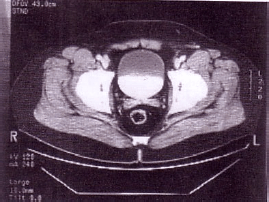

Em um estudo tomográfico de Abdome e Pelve, foi obtida a seguinte imagem:

Pode-se afirmar que a imagem acima corresponde à série